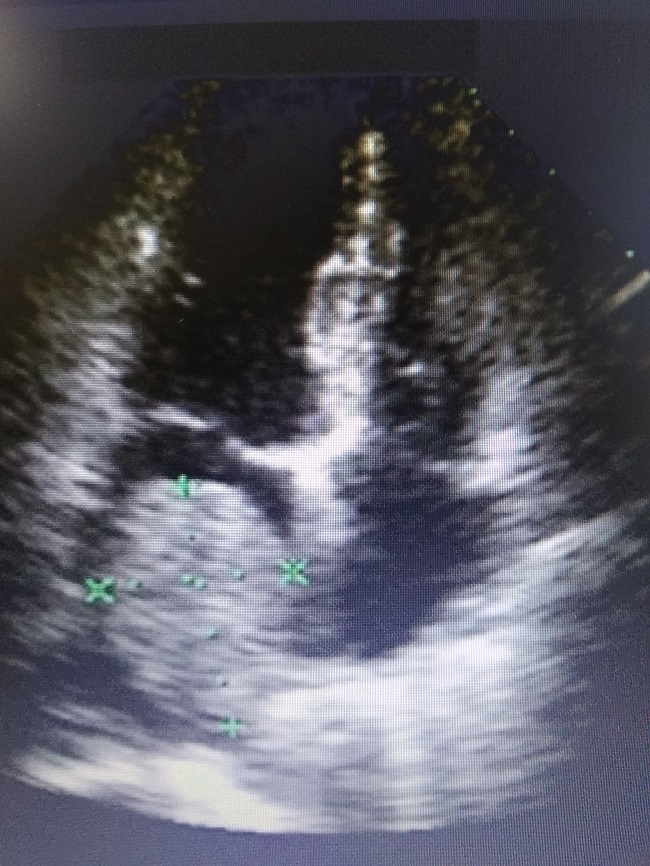

Во время этого же визита в клинику, пациентке Л. была проведена ЭХО-КГ, по данным которой врачом-кардиологом выявлена миксома (доброкачественная опухоль сердца) левого предсердия, занимающая 60-70% его полости.

Во время сокращения сердечной мышцы/миокарда на мониторе было видно, как опухоль полностью перекрывает атриовентрикулярное отверстие левых отделов/камер сердца (место, где кровь выталкивается из левого предсердия во время сокращения миокарда), перекрывая тем самым кровоток, что вызывает симптомы нестабильной стенокардии.